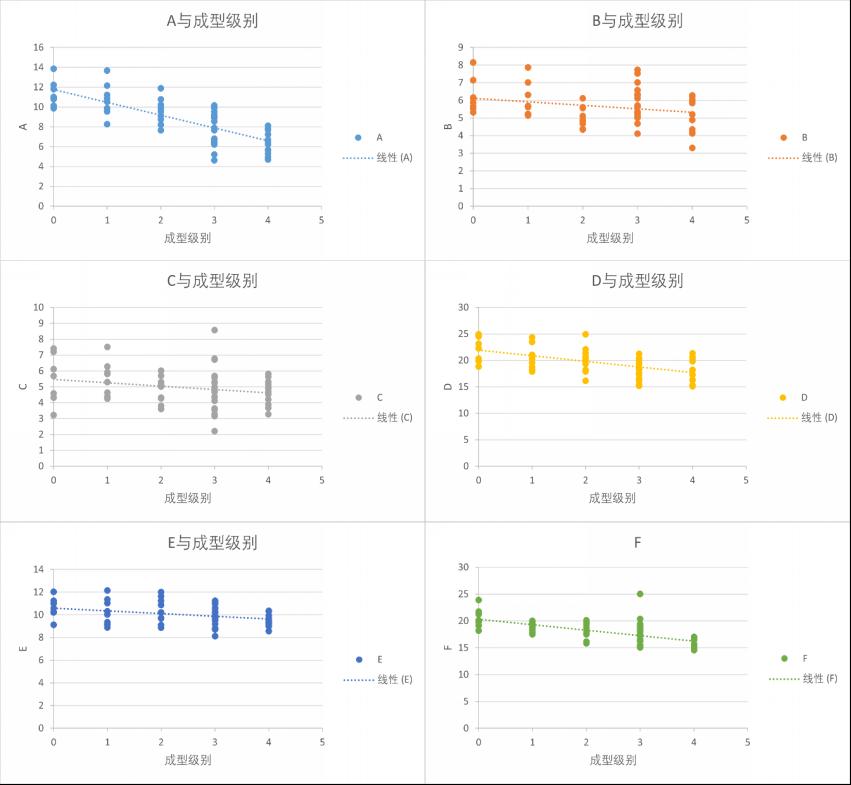

3���、A���、D����、F与椎间孔成型级别呈显著负相关��,且P <0.001��;E与椎间孔成型级别呈负相关��,且P =0.01�����;B与椎间孔成型级别呈负相关�����,且P <0.05���,见表格 2��, 图 9��。

图 9 A-F与成型级别散点图

2���、在成型级别的指导中��,可将测出的A作为主要指标����,D����、F作为次要指标���,B���、E作为参考指标��。将得到的5种测量指标与研究得出的数据进行比较����,术前即可对于L4-5节段成型级别的大小进行简单评估����,指导术中椎间孔成型的范围��。避免手术过程中成型不足造成髓核组织残留����,减压不充分等医源性因素所导致的症状缓解不明显或者降低手术过程中椎间孔过度成型所导致的腰椎不稳及慢性腰痛等症状���。